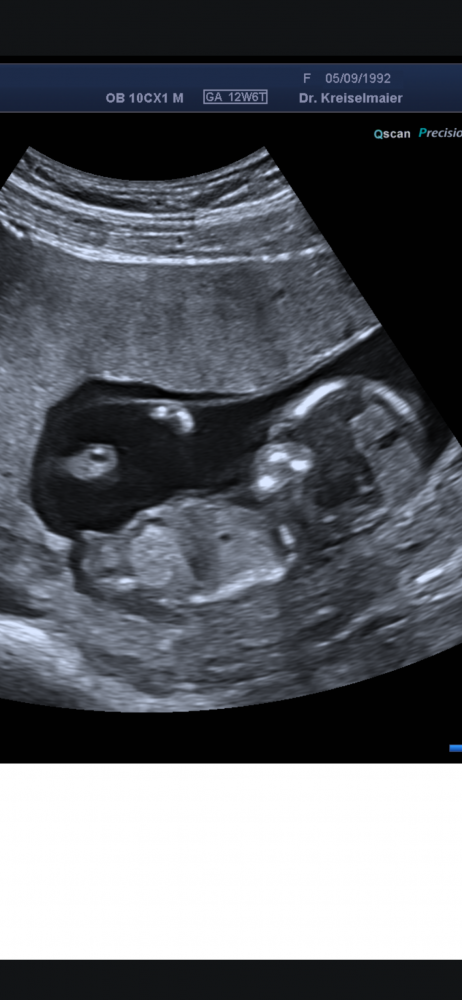

Hallo meine Lieben, waren heute beim Ultraschall SSW17

Das Geschlecht spielt bei uns keine Rolle, da wir bereits einen Jungen und ein Mädchen haben.

Aber aus reiner Neugier, was meint ihr anhand der Bilder, Mädchen oder Junge